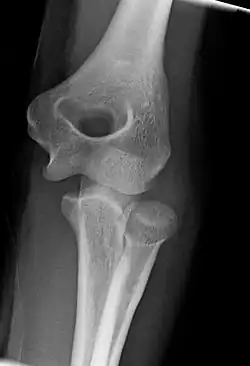

Normal radiograph; right picture of the straightened arm shows the carrying angle of the elbow

When the arm is extended, with the palm facing forward or up, the bones of the upper arm (humerus) and forearm (radius and ulna) are not perfectly aligned. The deviation from a straight line occurs in the direction of the thumb, and is referred to as the "carrying angle".[22]

The carrying angle permits the arm to be swung without contacting the hips. Women on average have smaller shoulders and wider hips than men, which tends to produce a larger carrying angle (i.e., larger deviation from a straight line than that in men). There is, however, extensive overlap in the carrying angle between individual men and women, and a sex-bias has not been consistently observed in scientific studies.[23]

The angle is greater in the dominant limb than the non-dominant limb of both sexes,[24] suggesting that natural forces acting on the elbow modify the carrying angle. Developmental,[25] aging and possibly racial influences add further to the variability of this parameter.